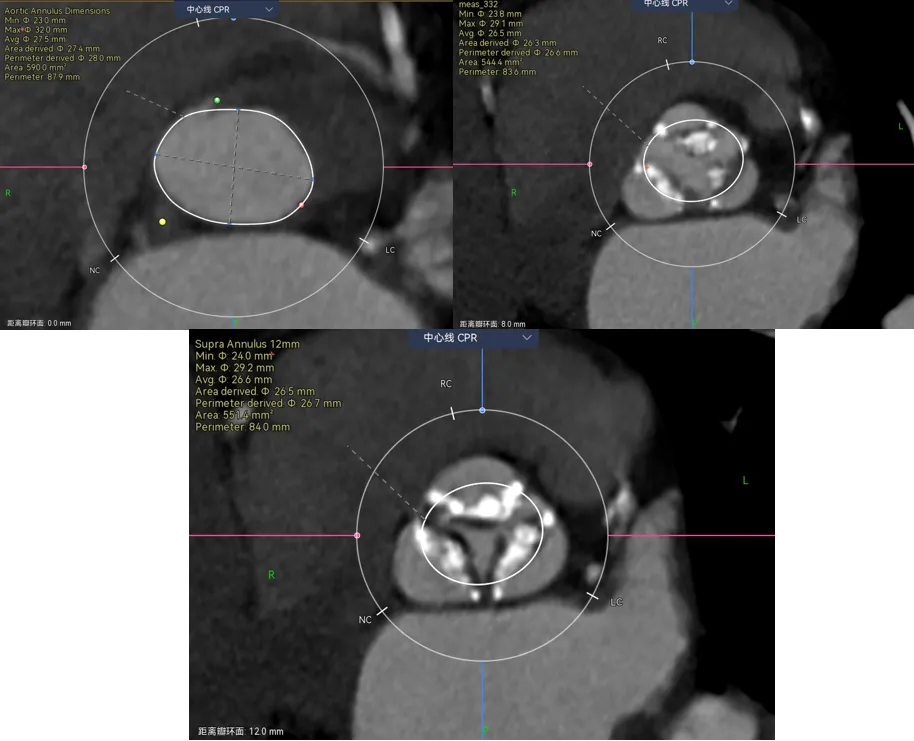

再来看一例三叶瓣的重度钙化对瓣膜的推挤,病例-4

遇见这种三叶瓣,边缘都有很重钙化的你会怎么画呢?瓣叶能推开么?要不要把边缘占满?这里考验的就是对钙化程度的综合理解了。刚刚也说了,瓣叶中间的钙化一般是可以推动的,除非连上了基底部有一大块的。而边缘的钙化,瓣膜往往没法占满。这就是钙化导致的瓣周漏的原因。

让我们来看看术前和术后预测的对比,预留的交界区域完全正确,瓣膜无法填满三个瓣叶的交界边缘,从瓣环到瓣上12mm都留有一丝缝隙,这类病例除非充分后扩贴一贴,不然多少都会有一点儿漏,术前可以充分预估到。